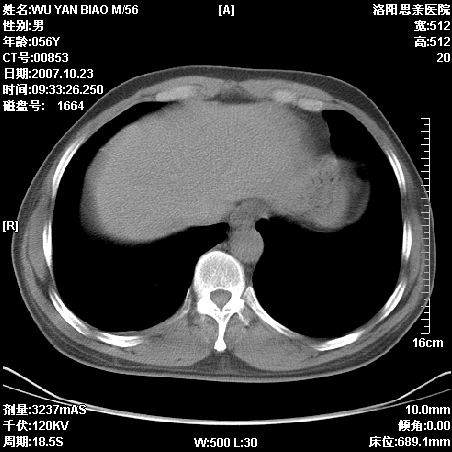

标题: CT10160:M56Y,体检发现,病人无不适,病人随访中 [打印本页]

标题: CT10160:M56Y,体检发现,病人无不适,病人随访中

后上纵隔占位,与肺交界清,宽基底附着脊柱,密度均匀,局部骨质无明确改变.

考虑;神经源性肿瘤,---起源交感n链?,不除外肠源性囊肿.

1、病灶在后纵隔脊柱旁沟内,此处是神经原性肿瘤的好发部位

2、病灶边缘光滑整齐,更说明病灶来于纵隔,由于有胸膜的包裹所以才导致这么光滑的边缘

3、病灶内的密度均匀